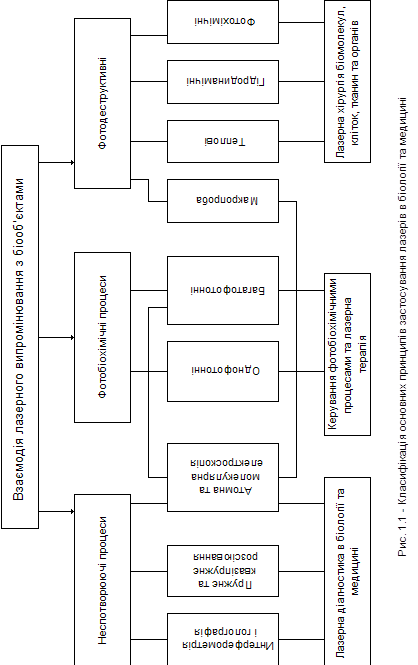

Використання лазерів у біології та медицині може здійснюватися в кількох напрямках, одним з яких можна вважати розробку на основі лазерної техніки приладів та методів для виявлення, ідентифікації, дослідження будови біологічних об^єктів, а також для вивчення природи процесів, що відбуваються в них [4].Застосування лазерів у біології і медицині засновано на використанні широкого кола явищ, пов"язаних із різноманітними проявами взаємодії світла з біологічними об"єктами. Лазерне випромінювання, так само як і звичайне світло, може відбиватися, поглинатися, розсіюватися, перевипромінюватися біологічним середовищем, і кожний із цих процесів несе інформацію про мікро- і макроструктуру цього середовища, рух і форму окремих його складових. Червоне, інфрачервоне (ІЧ) та ультрафіолетове (УФ) світло можуть надавати фотобіохімічну дію. Яскравими прикладами цього є фотосинтез рослин і бактерій, а також механізм зору. Високоінтенсивне світлове випромінювання ультрафіолетового (УФ), видимого червоного та інфрачервоного (ІЧ) діапазонів довжин хвиль робить руйнівну (деструктивну) дію на біологічні об"єкти. Необхідні інтенсивності можна створити і не тільки за допомогою лазерів [3,4]. Таким чином, процеси, що характеризують види взаємодій лазерного випромінювання з біооб"єктами, можна розділити на три групи. До першої відносять усі неспотворювальні взаємодії (принаймні, у межах похибок вимірів, що не здійснюють помітної дії на біооб"єкт), до другого - процеси, у яких виявляється фотохімічна дія, і до третього - процеси, що призводять до фотодеструкції. На рисунку 1 подана класифікація основних принципів застосування лазерів у біології і медицині, що враховує зазначені групи процесів.